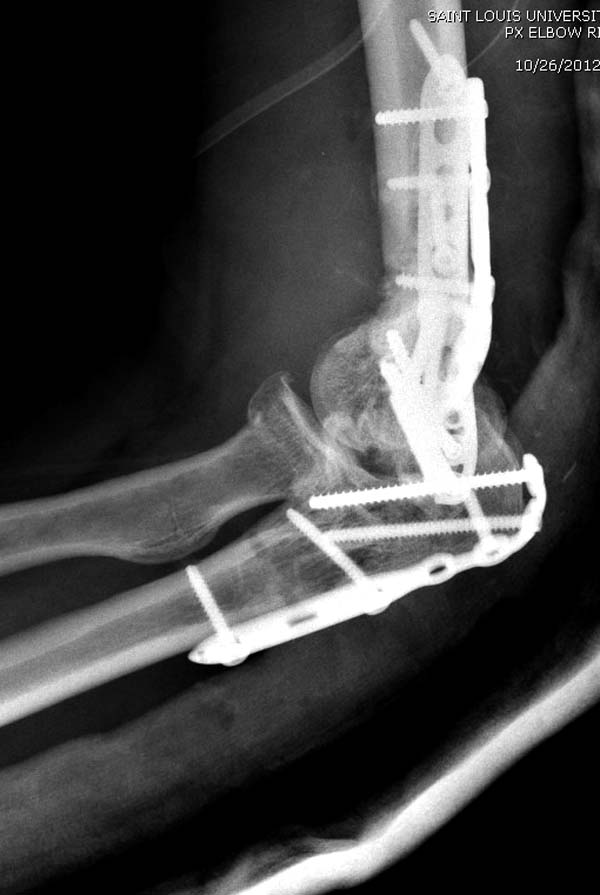

Разработаны различные концепции установки пластин на дистальное плечо: две параллельные в 180 или под углом в 90 градусов. Почти все компании имеют все варианты пластинок, а Acumed признает так называемую Keystone concept http://www.acumed.net/distal-humerus-plates

В данном случае надо делать ревизию. Среди остальных осложнении ложный сустав локтевого отростка лечить легко, фиксация пластиной и костный графт. Здесь в первую очередь надо создать конгруентость локтевого сустава и вместо толстых шурупов взять тонкие 2.5-3.5 мм. Это как раз случай, когда качество работы зависит не только от опыта хирурга, а и от наличия современного материала по рукой.

Примеры: первому более 15 лет фиксирован шурупом и tension band technique, а второй перелом открытый больной 80 лет, после наружного фиксатора в первом этапе и окончательная фиксация вторично. Третьий раз внесуставная остеотомия...